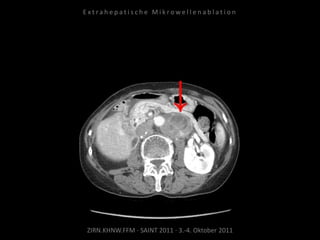

Patient: Weiblich, 66 Jahre

Diagnose: Ovarial-Ca,

progrediente retroperitoneale

Lymphome, u.a. am Truncus coeliacus

und der Arteria mesenterica superior.

Zunehmende Drucksymptomatik im

Oberbauch.

Bildgebung vor MWA:

CT 09.09.2010

Situation:

Tumorerkrankung mit ausgedehnter

Metastasierung. Schmerzsymptomatik

durch Metastasen am Truncus coeliacus.

Ziel:

Druckreduzierung durch Reduzierung

der Tumorlast, thermische Reduktion

der Schmerzfasern am Truncus, dadurch

Reduzierung der hierdurch bedingten

Beschwerden. Kein kurativer Ansatz.

Ablation am 07.10.2010:

Je eine Nadelposition von links und

von rechts.

Kontrolle:

CT 08.10.2010

CT 05.11.2010

Kein Progress im abladierten Areal.

Erfolgreiche Schmerztherapie.